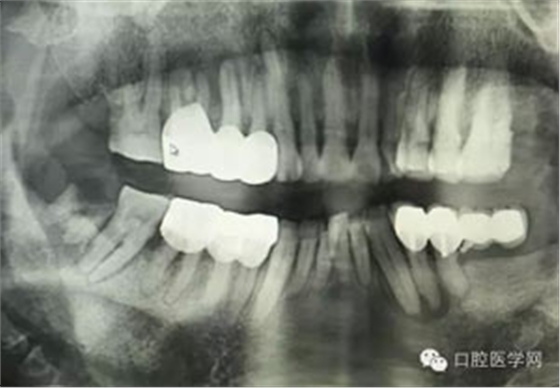

病例1:患者迫切希望保留自己的這一顆牙齒,根尖周陰影比較大,二度松動(dòng).而且旁邊有種植修復(fù)體,和患者溝通好后,治療好后觀察一個(gè)月后冠修復(fù),因?yàn)橛蟹N植的后期修復(fù),所以有了機(jī)會(huì)觀察,術(shù)后三個(gè)月和術(shù)后四個(gè)月,根尖恢復(fù)的還算不錯(cuò),希望能夠繼續(xù)觀察下去.這樣子的病例,做的時(shí)候我們一定要非常的小心,和患者要有充分的溝通以及不同科室的溝通然后決定怎么樣做比較好,假如就是出現(xiàn)了問題,到時(shí)候我們也比較好處理些,免得我們自己到時(shí)候不好收?qǐng)觥?/span> 病例2:364647中齲的樹脂充填,現(xiàn)在樹脂的充填材料非常之多,有些時(shí)候,我們感覺有了好的材料我們就可以做出好的修復(fù),可是這是在我們有扎實(shí)的基本功的基礎(chǔ)上的,我們可以沒有那么好的樹脂,那么多的顏色選擇,修復(fù)的那么的逼真,但是我們至少要恢復(fù)患者牙齒的功能,將腐質(zhì)去除干凈,薄壁弱尖消除掉,選擇好適應(yīng)癥,給患者以盡可能好的修復(fù)。 來源于KQ88